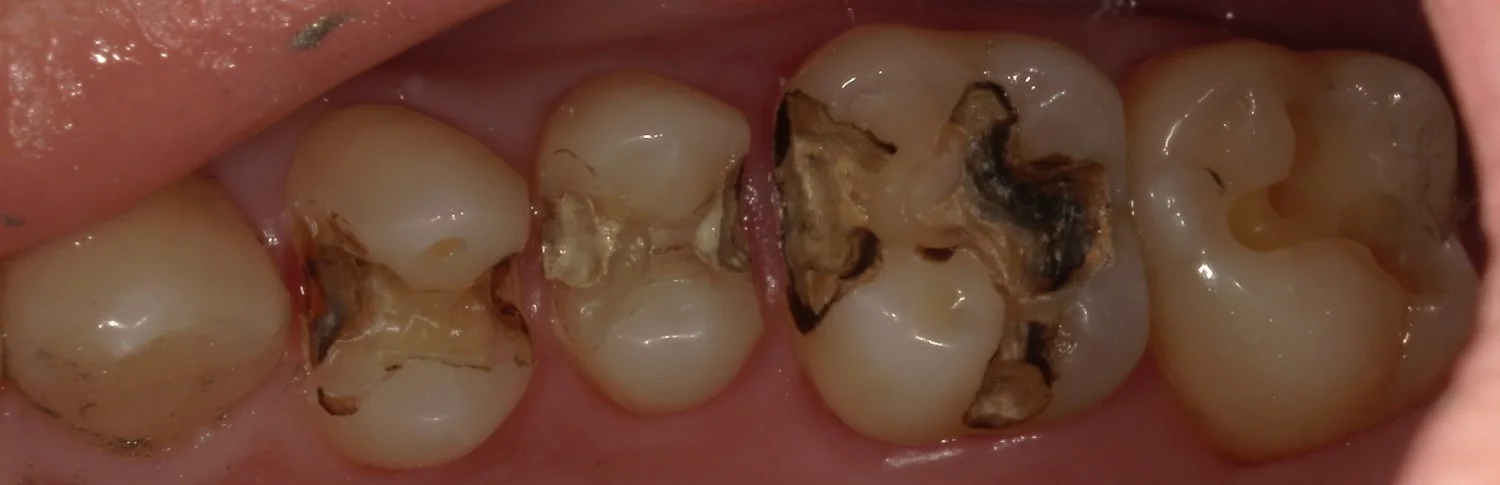

まずは術前ですね。

今回は神奈川県からの来院の為、一気に4本を行っています。

処置を行ったのは金属が入っている3本と、右側一番奥の白い詰め物が入っているところです。